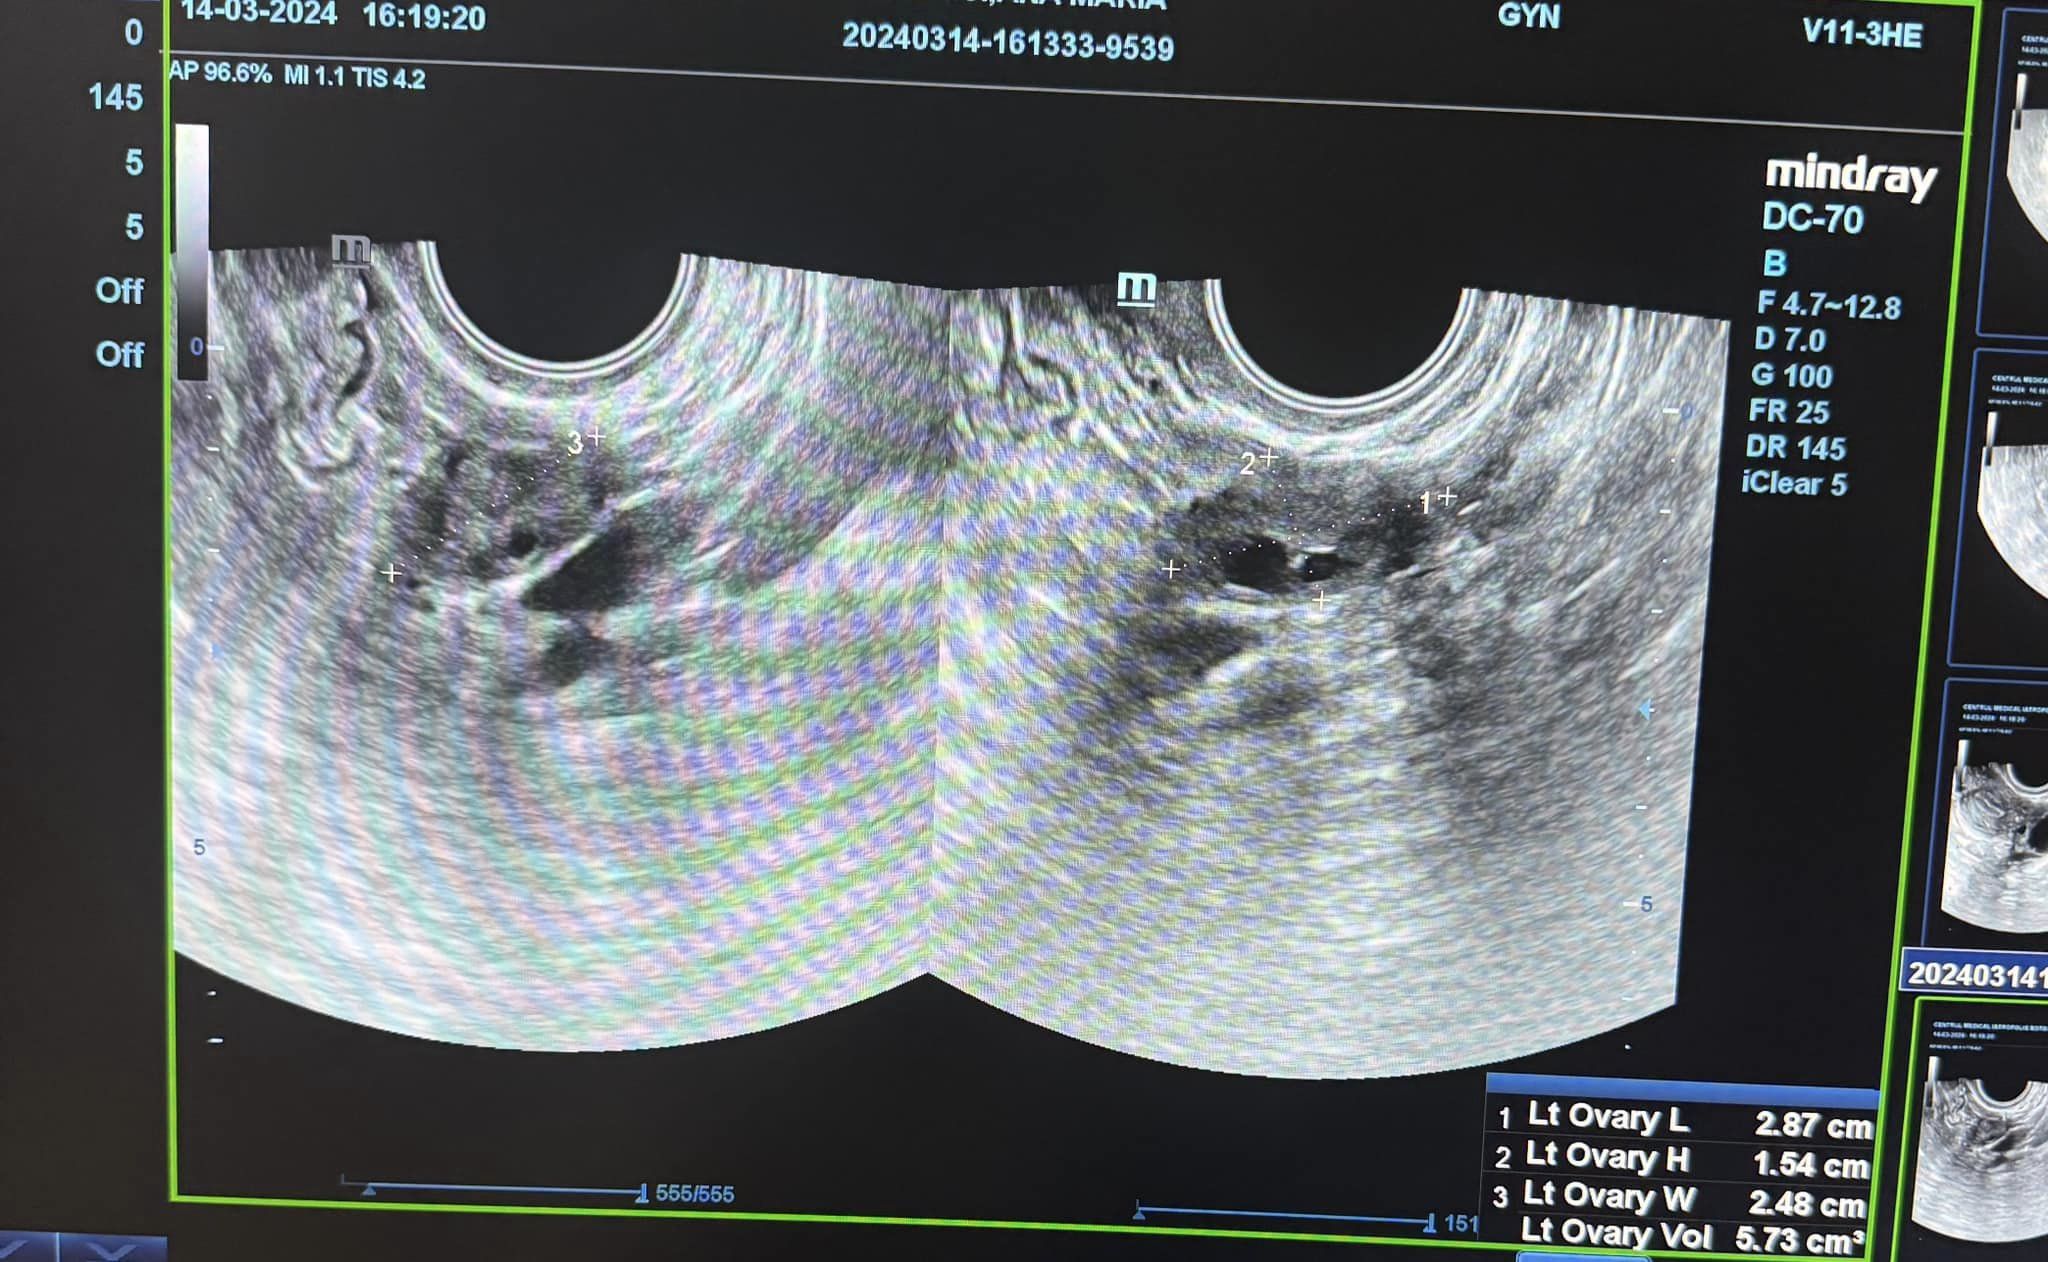

Pacientă în vârstă de 28 ani care s-a prezentat la medic pentru dereglări menstruale și dureri abdominale, și pe care am văzut-o prima dată în luna noiembrie, speriată fiind de diagnosticul primit și de faptul ca i s-a recomandat să se opereze pentru a scoate chistul, pe care am revăzut-o la control, după aproximativ 4 luni de tratament.